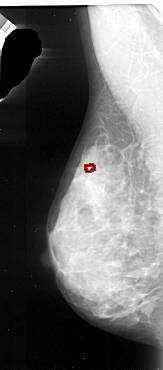

A_1092_1.LEFT_MLO

LEFT_MLO LINES 5536 PIXELS_PER_LINE 2431 BITS_PER_PIXEL 16 RESOLUTION 42 OVERLAY

FILE: A_1092_1.LEFT_MLO.OVERLAY

TOTAL_ABNORMALITIES 1

ABNORMALITY 1

LESION_TYPE CALCIFICATION TYPE PUNCTATE DISTRIBUTION CLUSTERED

ASSESSMENT 4

SUBTLETY 1

PATHOLOGY MALIGNANT

TOTAL_OUTLINES 1

BOUNDARY